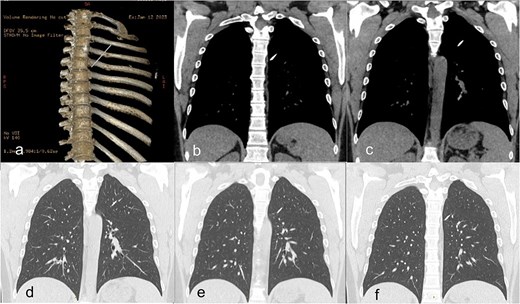

A 38-year-old right-handed male, active smoker and non-physical worker without sports activities had a car accident in Tunisia. A displaced left mid-clavicular fracture was fixated with a single intramedullary pin. No further information about the accident and initial intervention were available. Twelve years later, the patient presented in our clinic with left thoracic discomfort and an intermittent dry cough. Chest X-ray showed a broken wire with the proximal half still in the clavicle and the distal half inside the left chest. A computed tomography (CT) scan confirmed that the wire had broken at the level of the clavicular fracture, which had consolidated in Z-deformation while the distal half of the pin had migrated into the left lung, transfixing the posterior part of the left upper lobe, passing through the fissure into the apical segment of the left lower lobe. The sharp point of the pin pointed in the direction of the vertebral column directly behind the descending aorta (Fig. 1). The imaging showed no clear inflammatory reaction or abnormalities of the lung parenchyma around the pin.

(a) Preoperative CT scan with 3D-reconstruction of skeletal structures and Kirschner wire. (b–f) Distal pin in the left lung transfixing the left upper lobe and fissure into the left lower lobe without pneumothorax.